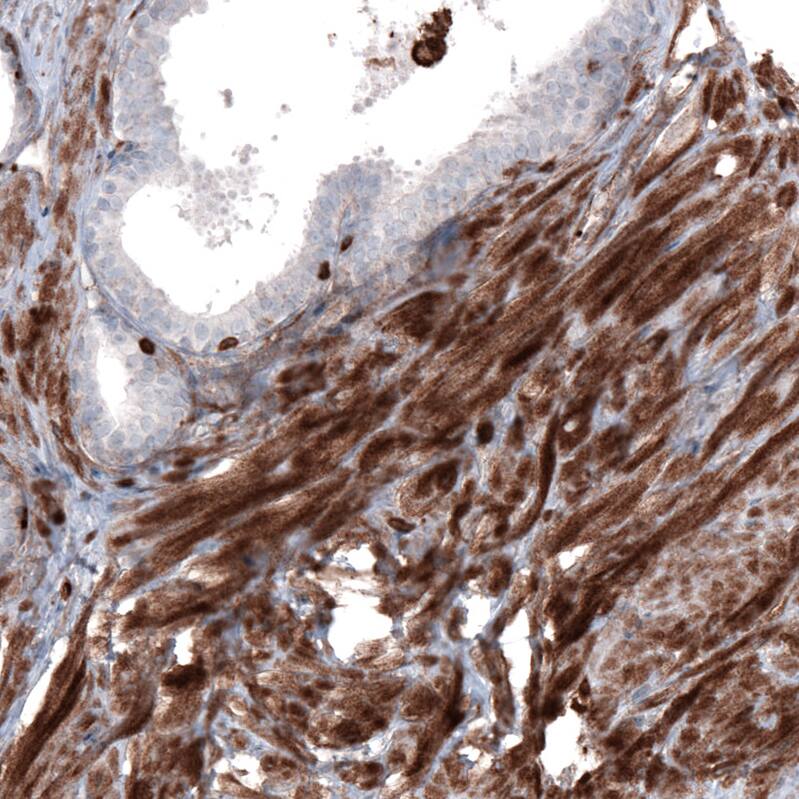

Staining of human prostate shows strong cytoplasmic positivity in smooth muscle cells.